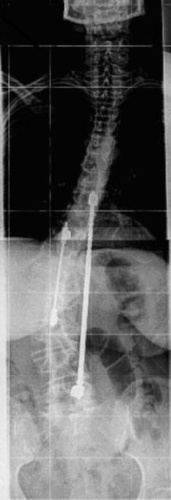

hier die Bilder vom September 2011.

auf dem ersten Bild kann man die gelöste Schraube erkennen, die ich manchmal durch stichige Gefühle spüre.. aber nicht immer..

man kann auch den Stabbruch auf dem zweiten Bild besser erkennen der sich recht mittig befindet, leider musste ich die Bilder verkleinern was die Sicht um einiges erschwert.. ABer danke für dein Rat minime.

Aber jetzt könnt ihr ja besser beurteilen, ob ich nach Harington oder einer anderen Methode operiert worden bin..

Gruss, Becca

skoliose1.jpg

skoliose1.jpg (24.12 KiB) 5423 mal betrachtet

skoliose2.jpg

skoliose2.jpg (25.04 KiB) 5423 mal betrachtet

Das sind keine Harrington-Stäbe, vgl. den folgenden Anhang.

Nee, da ist eigentlich nicht viel Ähnlichkeit. Ein Harrington-Stab wird mit zwei Haken an den Fortsätzen der Wirbel befestigt, aber die Stangen auf den Röntgenbildern von Dir sind mit Pedikelschrauben fixiert, die direkt in den Wirbelkörpern sind. Das ist ein ganz anderes Prinzip. Der genaue Implantattyp müßte irgendwo in den OP-Unterlagen oder im Arztbericht zu finden sein.